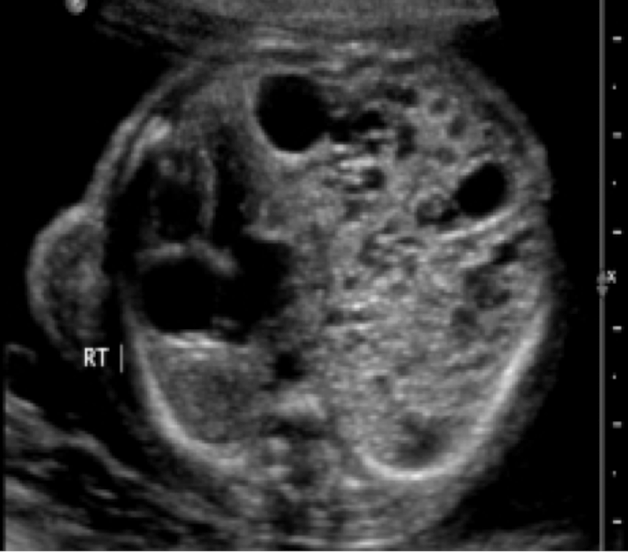

normal or abnormal

abnormal: CCAM/CPAM